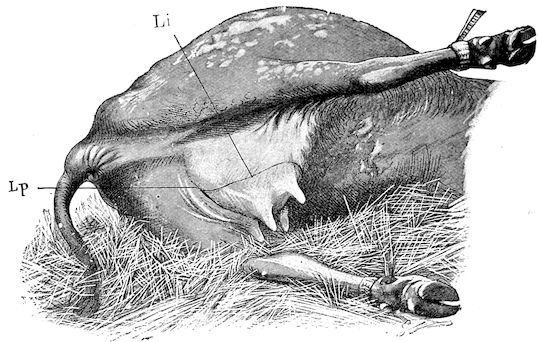

Fig. 1.—Rachitis in a young goat.

Fig. 1.—Rachitis in a young goat.